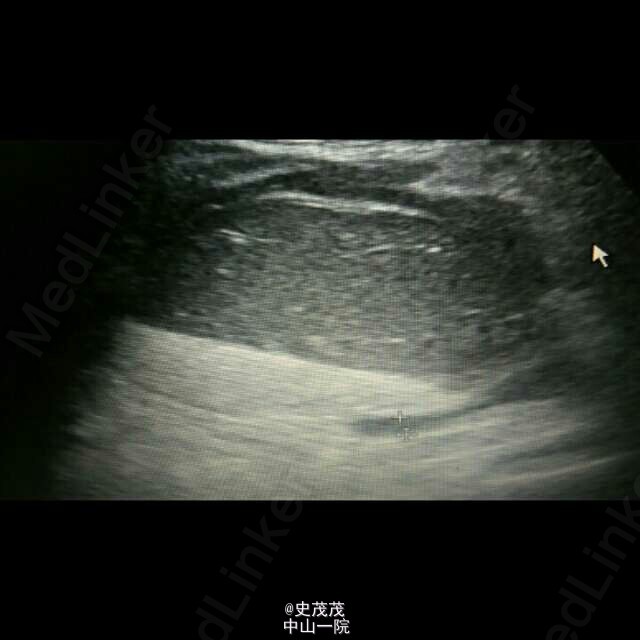

卵巢畸胎瘤蒂扭转

以“下腹痛5天”急诊收入院,外院B超、CT提示卵巢畸胎瘤可能,遂转入我院。已手术,术中见巨大畸胎瘤,内含多量黄色浑浊液,见毛发。快速冰冻,提示含有牙齿。 B超不怎么会看,有个问题:按顺序的发的B超图片,里面有2-3-2个无回声洞,这几个无回声洞可提示蒂扭转吗?(那个洞是输卵管管腔吗?)